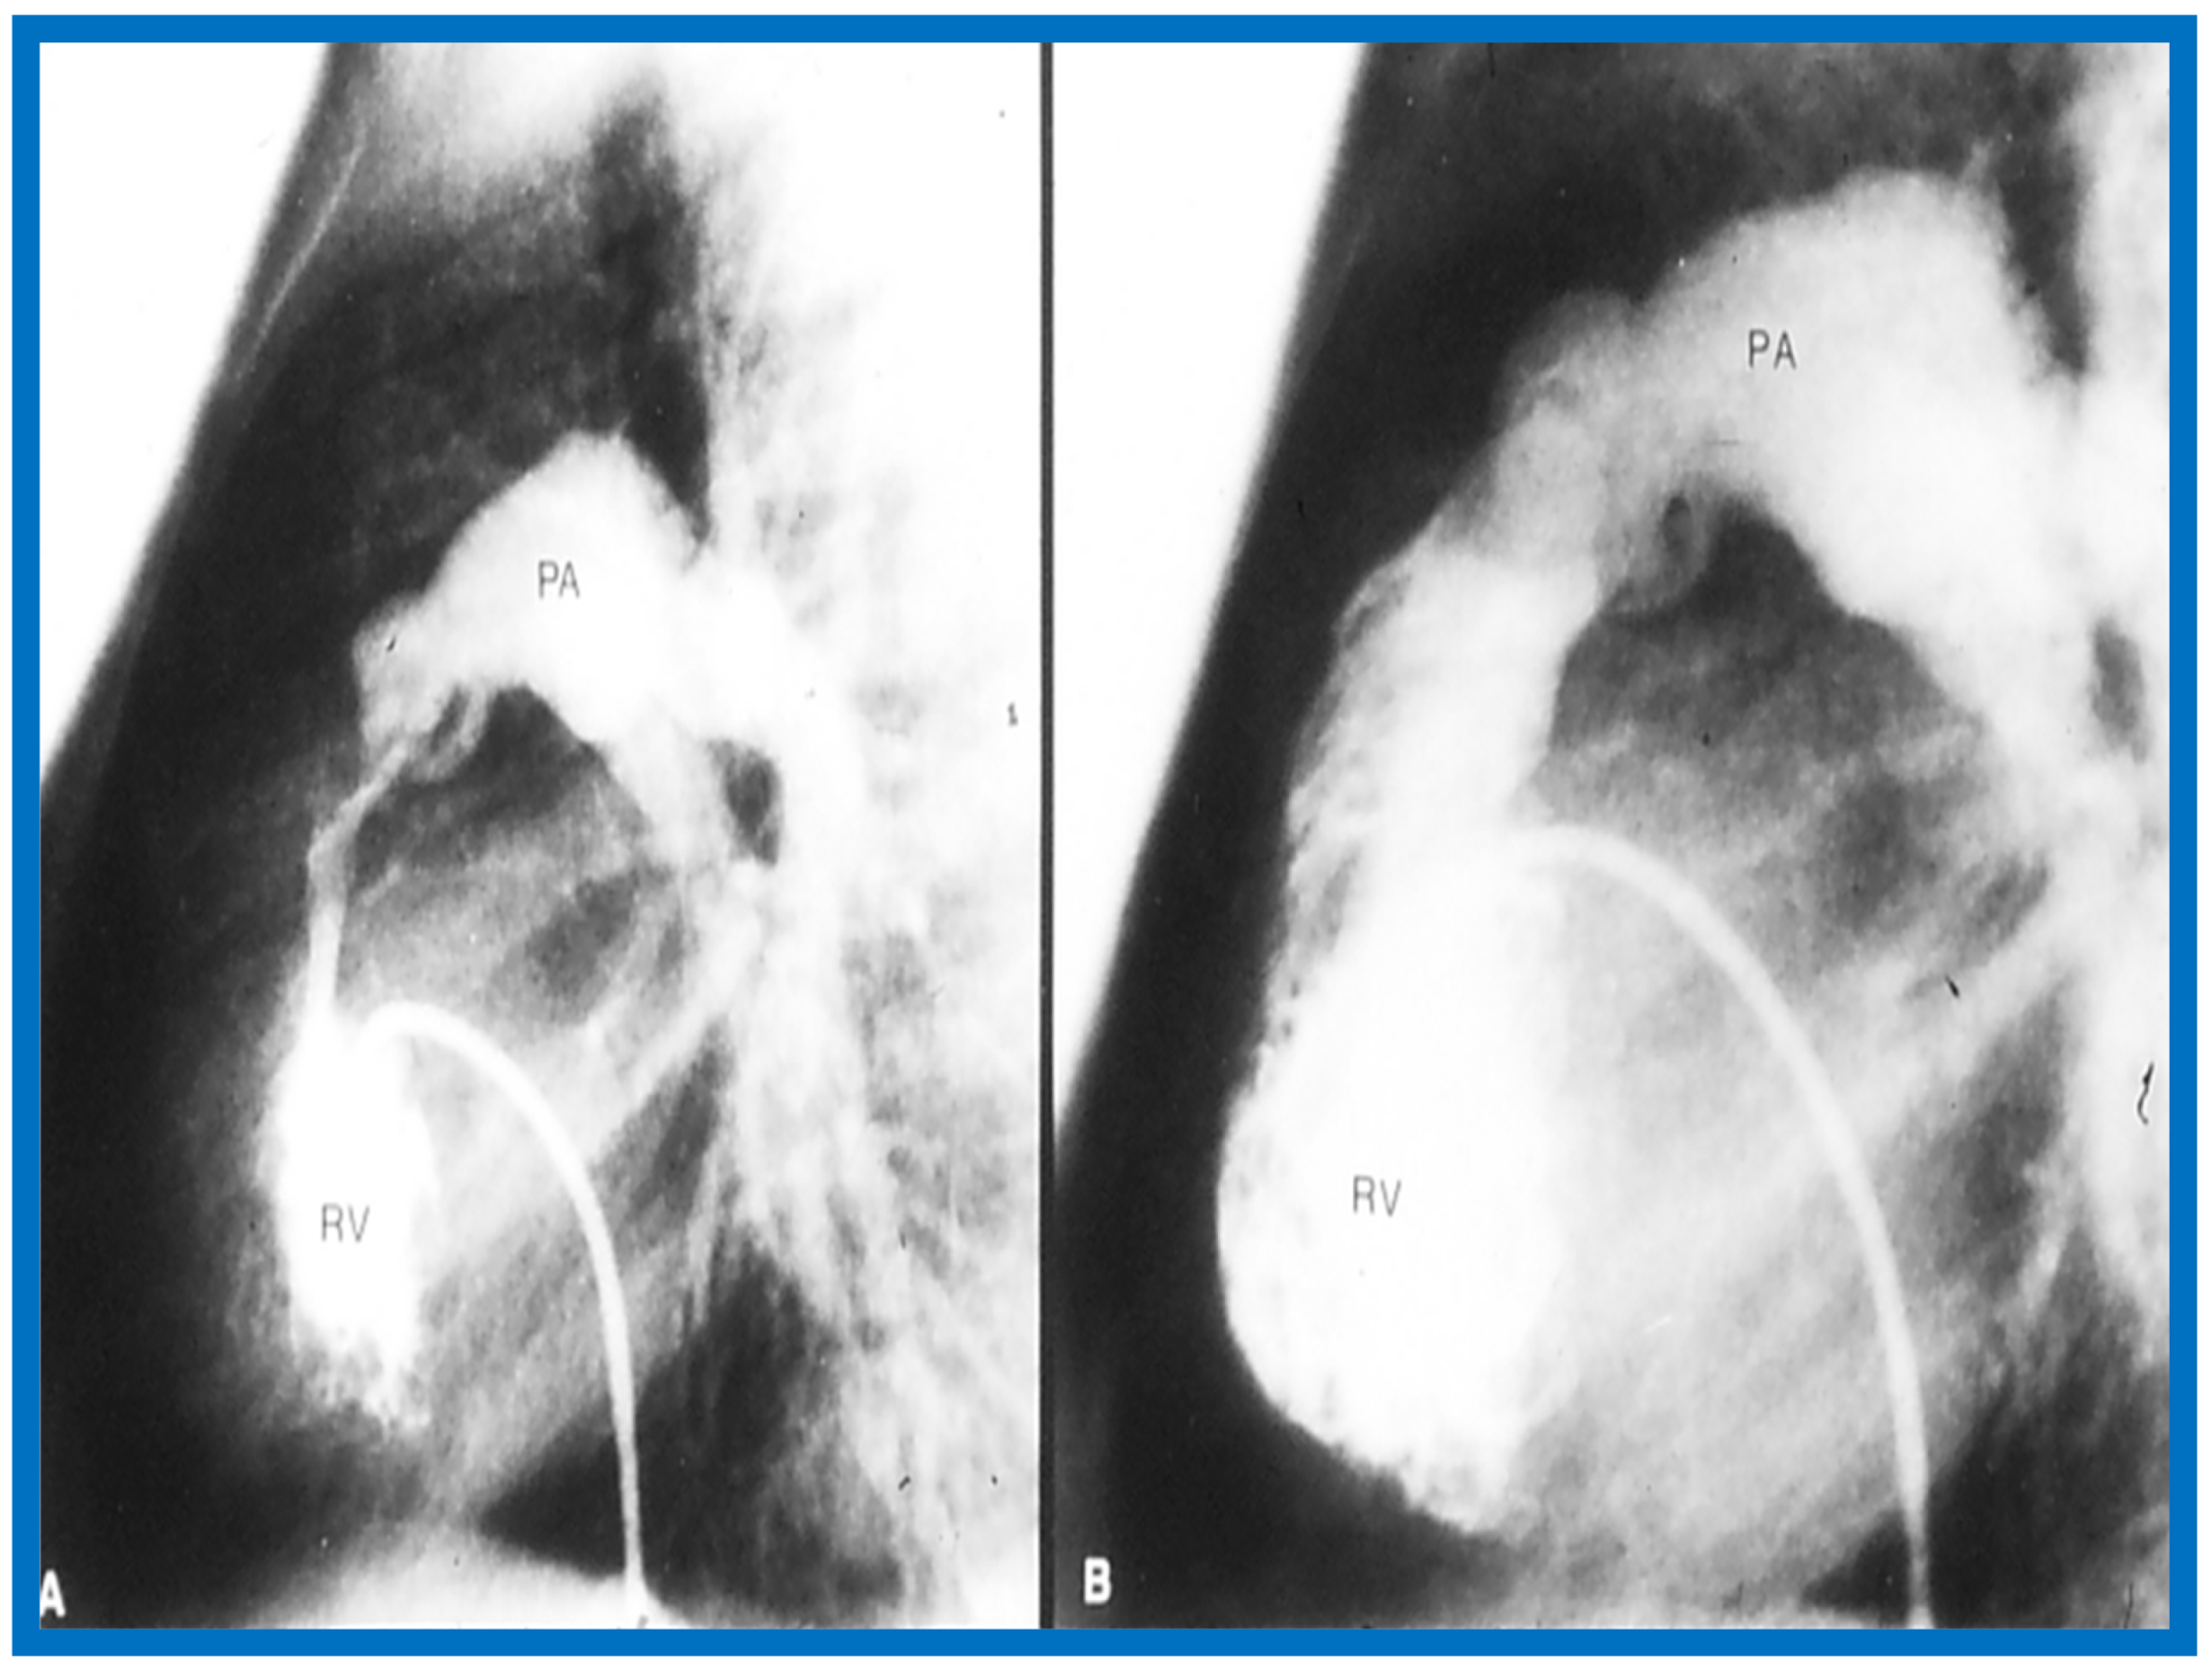

13. Doppler in the Prediction of Pressure Gradients in Valvar Pulmonary Stenosis

The relationship of Doppler with catheterization-measured pulmonary valve pressure gradients was studied by examining 35 pairs of such measurements, made within 24 h of each other [14]. The correlation coefficient was 0.61 (Figure 46); this improved to 0.91 (Figure 47) after removal of the five patients with severe stenosis (gradients of 94 to 190 mmHg) and one patient with severe infundibular stenosis (Figure 48 and Figure 49).

Figure 48.

Selected right ventricular (RV) cineangiographic frames from lateral projection demonstrating severe infundibular constriction immediately following balloon pulmonary valvuloplasty (A) which has resolved (B) during a study six months later. PA, pulmonary artery. Reproduced from Rao P.S. [14].